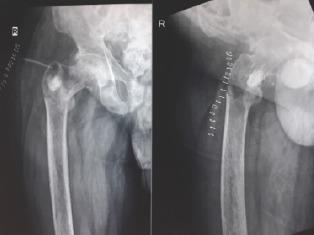

A 42-year-old male presented with complaints of low back pain for the past 4 years and inability to walk for the past 3 years. Blood investigations showed hypophosphatemia and elevated serum alkaline phosphatase. Radiographs and magnetic resonance imaging revealed features of osteomalacia. DOTONAC PET-computed tomography (CT) showed a lesion in the greater trochanter suggestive of a phosphaturic mesenchymal tumor. CT-guided biopsy of the lesion was done which confirmed the diagnosis. The tumor was resected by intralesional methods (burring and cementation) with correction of hypophosphatemia by oral phosphorus supplementation. Patient clinically improved and was able to walk with support at the time of discharge.

Phosphaturic tumor was localized to be in the posterior aspect of the right greater trochanter. To find the tumor was a major diagnostic challenge involving various diagnostic modalities. The occurrence of such a condition is rare and it may take even years to correctly diagnose the disease.